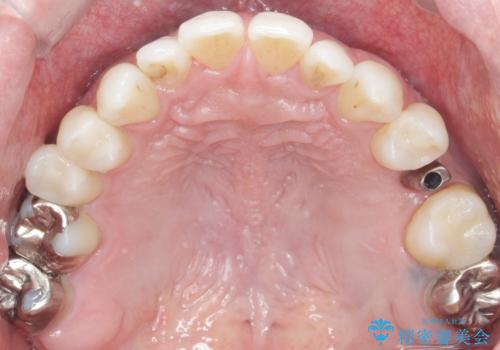

患者様のご希望により、抜歯後インプラント治療を行いました。

骨の厚みが不足していたため、インプラントの埋入と同時にソケットリフト(上顎骨に骨を増やす手術)を行いました。